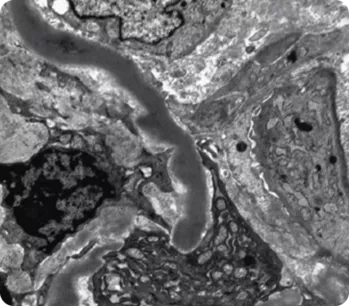

C3-гломерулопатия (C3ГП) представляет собой хроническое редкое заболевание почек, характеризующееся нарушением системы комплемента и отложением фракции C3 в биоптате почечной ткани. Это состояние включает два подтипа: болезнь плотных депозитов (БПД) и С3-гломерулонефрит (C3ГН), различающиеся по локализации отложений C3b, обнаруживаемых при электронной микроскопии.

• Мезангиальные и внутримембранные, протяженные, электронноплотные, осмофильные отложения6—8.

• Мезангиальные, субэндотелиальные, субэпителиальные и (или) внутримембранные отложения6—8.

Электронная микроскопия10

Электронная микроскопия

• Электронно-плотные отложения в мезангии вдоль ГБМ.

• Необходима электронная микроскопия для однозначного определения БПД и C3ГН1.